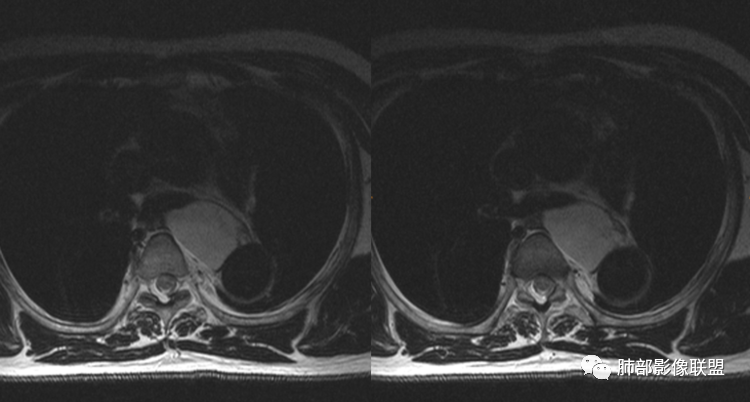

MR所见也差不多。

可能:食道囊肿,关系密切,但是直接依据不明显。

支气管囊肿、神经节细胞瘤,还有就是淋巴管囊肿。没有明确的依据